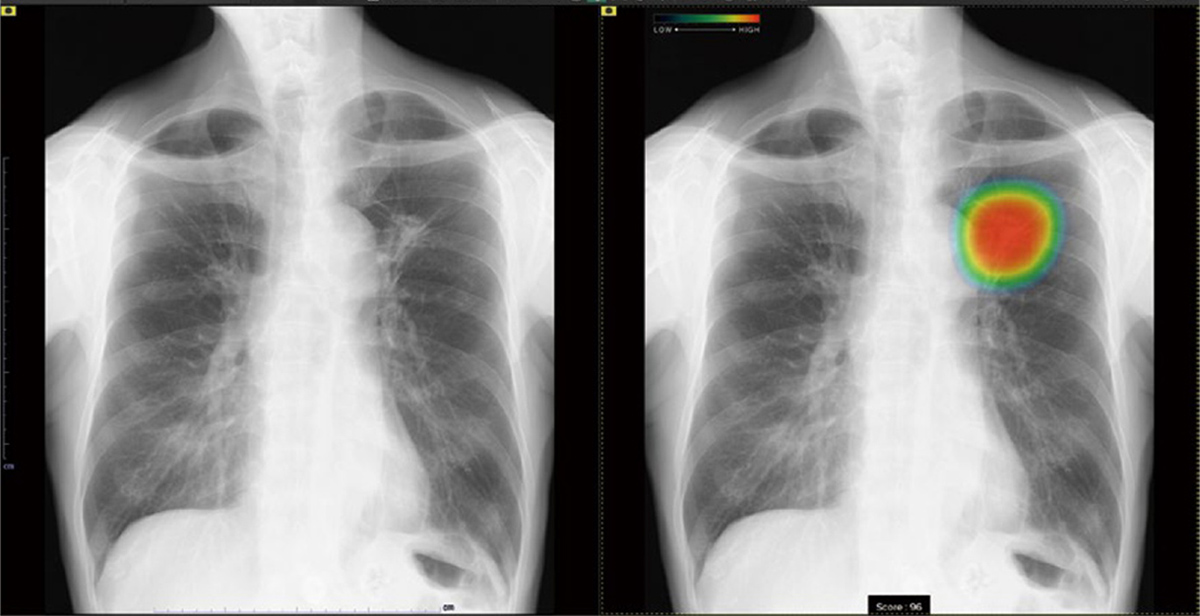

AIは検出した病変部位を「ヒートマップ」という色付きの地図のように表示します。

赤や黄色で示された部分は「AIが注目している箇所」であり、医師がより詳しく確認すべきポイントを視覚的に示します。

胸部X線画像では、AIが肺野(肺の領域)に丸い影を検出し、ヒートマップで示しています。早期発見により、適切な治療方針を早く立てることが可能になります。